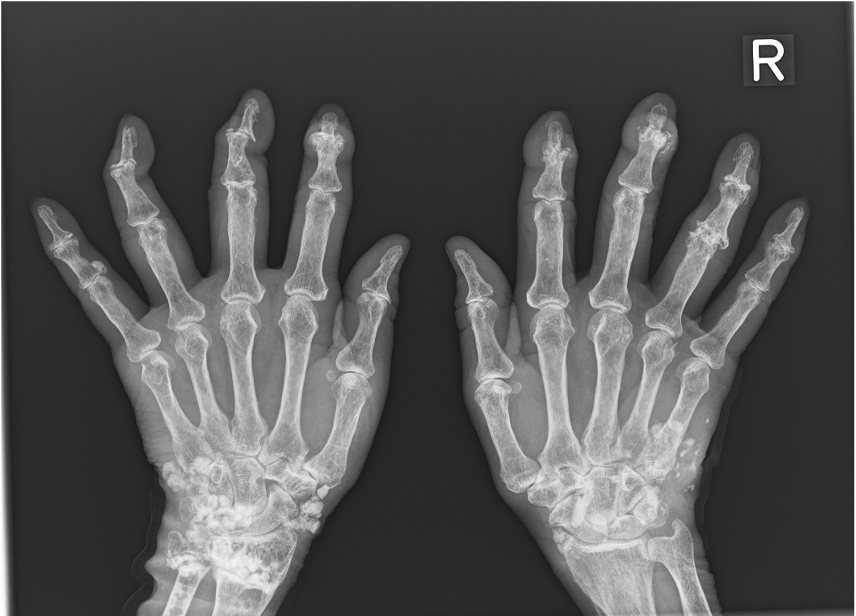

“Hand Calcinosis Cutis Associated with Psoriatic Arthritis: Impact of COVID-19 Flare on Surgical Outcome Assessed by the Michigan Hand Questionnaire”

が Plastic and Reconstructive Surgery – Global Open にアクセプトされた。本報告は、乾癬性関節炎(Psoriatic Arthritis)に伴う手部石灰沈着症に対して外科的切除を行い、手に特化した患者自身の主観的評価ツール(MHQ: Michigan Hand Questionnaire) を用いて、術後の疼痛・機能・満足度の変化を longitudinal に追跡したものである。

- 本症例では石灰沈着の減量手術の術後3か月に MHQ スコアが大幅に改善し、特に「疼痛」「仕事動作」の項目で著明な上昇がみられた。一方で、COVID-19感染を契機に乾癬性関節炎の病勢が再燃し、13か月後にはスコアが再び低下している。この経過は、自己免疫疾患の病勢変動が外科成績の長期評価を難しくしていることを示している。

- Calcinosis cutis(石灰沈着症) は、皮膚や軟部組織に不溶性カルシウム塩が沈着する疾患群で、自己免疫疾患に随伴する「dystrophic type」が多い。

石灰沈着症にたいする外科的切除(石灰の減量術)は疼痛・整容改善をもたらすが、再発率は15〜78%と報告され、有効性に関するエビデンスは限られている。

本症例では、減量術後に一時的なMHQスコアの改善を示したが、原疾患の病勢変動により長期的評価は困難であった(手術成績の長期的検証における限界を示唆した)。